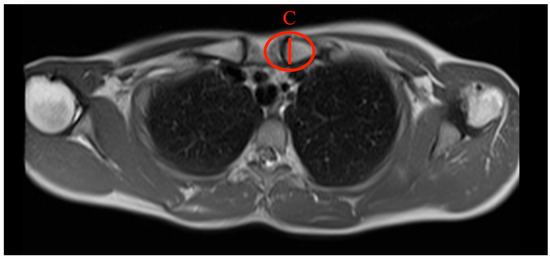

- Max. medial diameter: The distance was measured by drawing a line between the most dorsal and the most ventral points of the medial end of the clavicle (Figure 5).